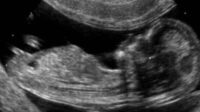

En Irlande, une ligne 24h/24 et 7j/7 pour demander un avortement

Les femmes qui recherchent un avortement médicamenteux pourront appeler une ligne téléphonique 24 heures sur 24, 7 jours sur 7 pour être conseillées et dirigées vers le médecin généraliste participant le plus proche, a appris l’Irish Independent. Seuls les médecins généralistes qui consentent à ce que leurs noms et adresses soient divulgués seront identifiés par téléphone (et seulement par […]